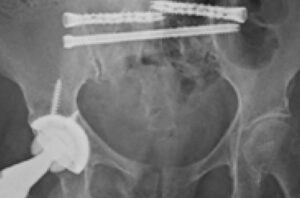

Dr. Brian Cunningham treats a sacral insufficiency fracture with iFuse TORQ TNT® and iFuse TORQ® implants for fracture fixation and SI joint fusion.

Dr. Brian Cunningham uses two iFuse TORQ TNT® implants for sacral fracture fixation and SI joint fusion following low-energy ground-level falls.